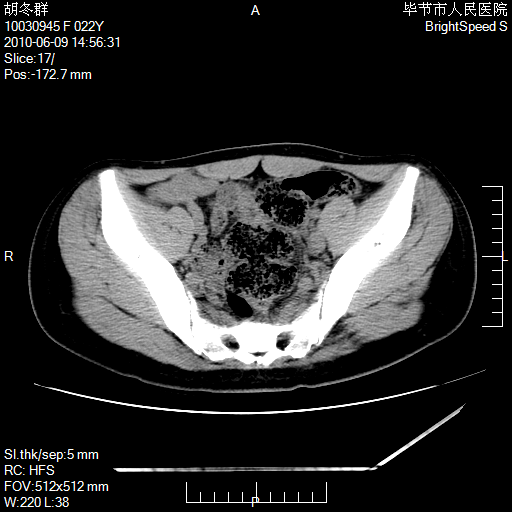

患者23岁,发现腹部包块3月。

我当时考虑重复膀胱,但我错得很厉害,我不明白,囊肿排尿后为什么能到膀胱位置。

左侧卵巢囊腺瘤或囊腺癌

盆腔内囊性占位性病变;考虑左侧卵巢囊腺瘤。

有分隔、壁薄,支持考虑左侧卵巢囊腺瘤。

左侧卵巢浆液性囊腺瘤。

有分隔、壁薄,支持考虑左侧卵巢囊腺瘤。排尿后,膀胱缩小,由于重力作用,肿块下移就到了膀胱位置,很好理解。